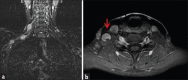

Schwannomas are benign soft-tissue tumors that arise from peripheral nerve sheaths throughout the body and are commonly encountered in patients with neurofibromatosis Type 2. The vast majority of schwannomas are benign, with rare cases of malignant transformation reported. In this pictorial review, we discuss the magnetic resonance imaging (MRI) appearance of schwannomas by demonstrating a collection of tumors from different parts of the body that exhibit similar MRI characteristics. We review strategies to distinguish schwannomas from malignant soft-tissue tumors while exploring the anatomic and histologic origins of these tumors to discuss how this correlates with their imaging findings. Familiarity with the MRI appearance of schwannomas can help aid in the differential diagnosis of soft-tissue masses, especially in unexpected locations.